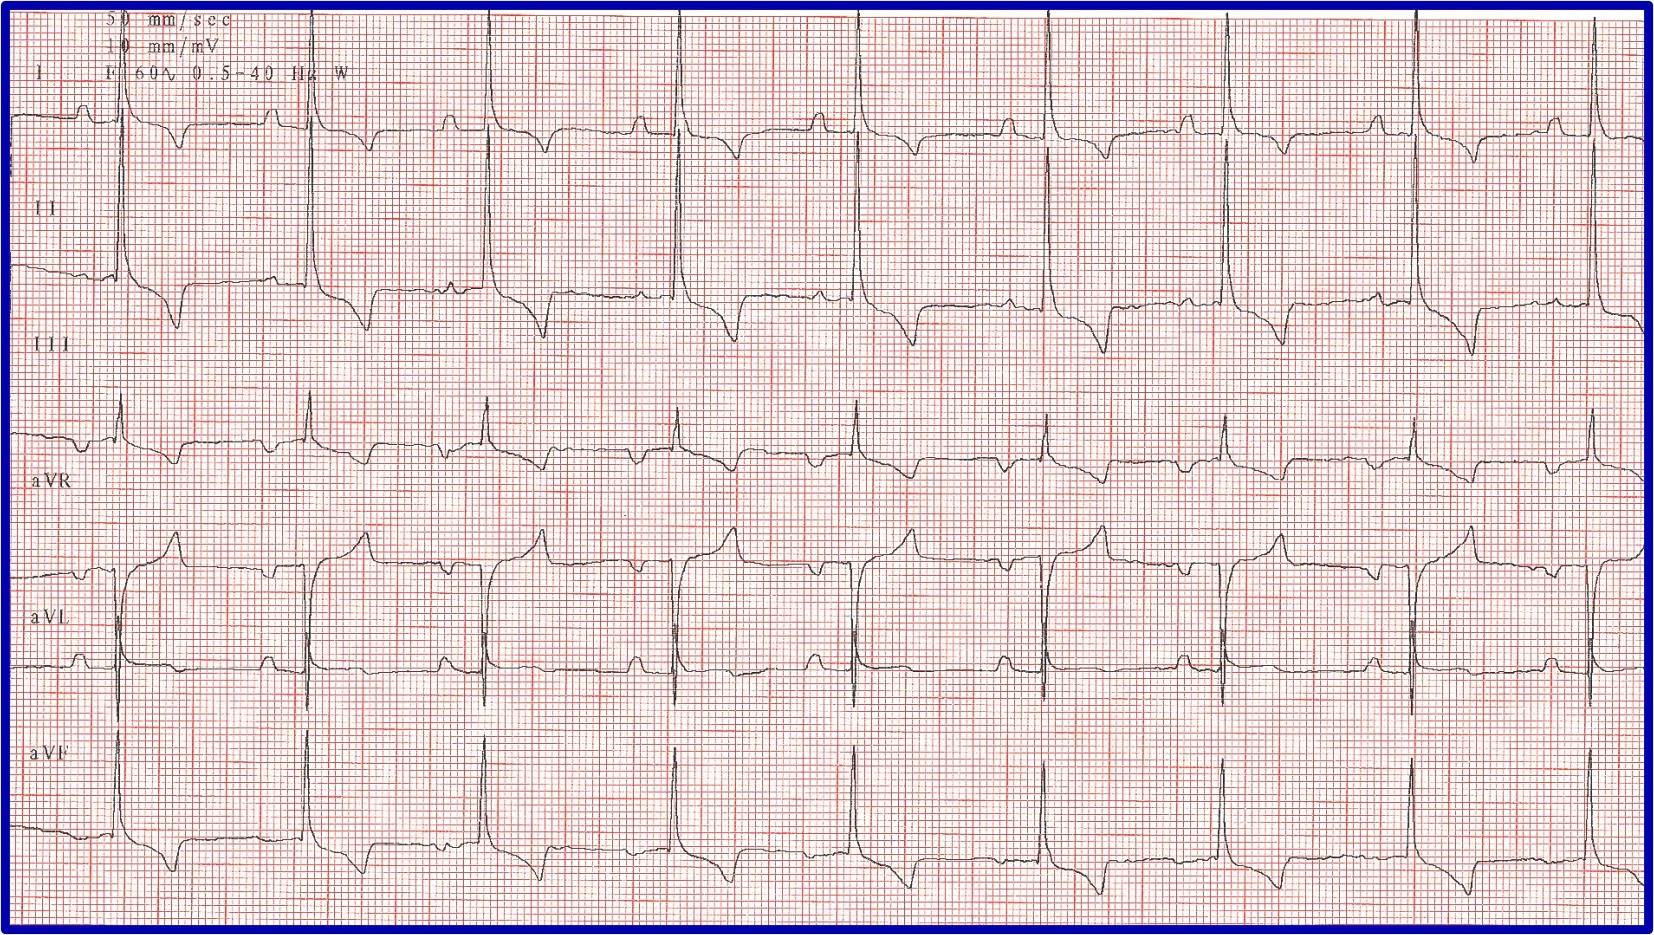

ECG features of atrial fibrillation (AF) include an irregularly irregular rhythm (variable RR intervals) with no identifiable pattern. P waves cannot be reliably identified, and heart rate is usually >200 bpm. QRS complexes typically appear to be supraventricular (ie, narrow and upright in lead II); however, some deep-chested breeds (eg, Doberman pinschers, Irish wolfhounds) develop wider QRS complexes with left ventricular enlargement instead of a tall QRS. The baseline may have irregular undulations (ie, fibrillation waves), but this is not a requirement for diagnosis. Fibrillation waves are not always present or identifiable, especially when the heart rate is fast. Aberrantly conducted beats may cause variation in the height and morphology of QRS complexes (Figure 9).

ECG in a patient with AF and aberrant ventricular conduction. A fusion beat (ie, simultaneous ventricular premature complex and normal sinus beat that results in an ECG trace that is a sum of the 2 vectors of depolarization) can be seen (circle). With AF, the atria fibrillate at 500 to 600 bpm; the AV node cannot discern whether it should conduct impulses and thus attempts to conduct all impulses but is unable to do so because it cannot depolarize and repolarize at that rate. Beats that do not appear supraventricular in origin were conducted when only parts of the conduction system were repolarized and ready to conduct an impulse from the AV node to the ventricular myocardium; these impulses take an abnormal pathway to the ventricle, resulting in the appearance of a wide, bizarre ventricular beat (arrows). For example, if the right bundle branch is repolarized and ready to conduct while the left bundle is still in a refractory period, an ECG complex that resembles an LBBB occurs. A different conduction pattern is possible with almost every beat, as the right and left bundles can be at different phases of refractoriness when each impulse is presented. This type of aberrant conduction is common with AF and important to recognize because it is not a dangerous ventricular rhythm and should not be treated with lidocaine or other ventricular antiarrhythmic therapy.

Irregularity can be difficult to identify when AF rate is >250 bpm. Multiple ECGs or ECGs with multiple leads (eg, 6- or 12-lead ECG) are needed. ECG recorded at a faster speed (eg, 50 mm/second) can also be helpful. A rapid, irregular supraventricular tachycardia without identifiable P waves should be considered AF until proven otherwise. If an alternative diagnosis is possible, AF should be ruled out first, as it is the most likely possibility.